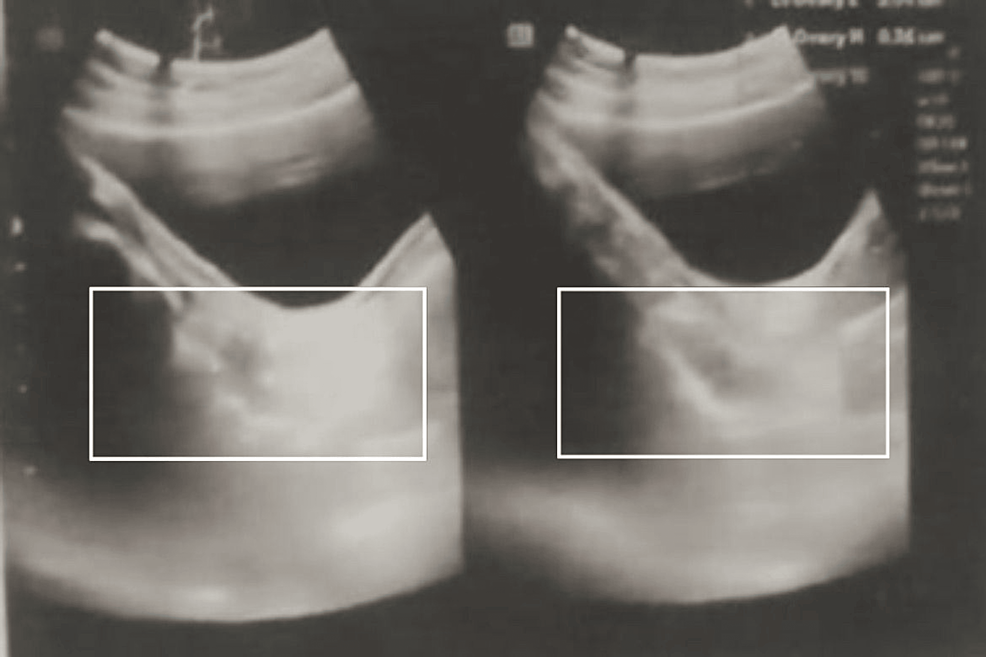

Cureus A Case of Chemical Pregnancy in a Female With Turner Syndrome

Cureus A Case of Chemical Pregnancy in a Female With Turner Syndrome Turner Syndrome Uterus And Ovaries Turner’s syndrome (ts) is depicted as a total or partial absence of one x chromosome that results in ovarian dysgenesis. Most women with turner syndrome have streak gonads or immature ovaries and manifest hypergonadotropic hypogonadism. It causes a variety of symptoms and features, like. Turner syndrome, also referred to as congenital ovarian hypoplasia syndrome is the most common sex. Turner. Turner Syndrome Uterus And Ovaries.

Cureus A Case of Chemical Pregnancy in a Female With Turner Syndrome Turner Syndrome Uterus And Ovaries Most women with turner syndrome have streak gonads or immature ovaries and manifest hypergonadotropic hypogonadism. Turner syndrome (ts) is defined as deficiency of all or part of the second sex chromosome in phenotypic females and is relatively common,. Turner’s syndrome (ts) is depicted as a total or partial absence of one x chromosome that results in ovarian dysgenesis. It causes. Turner Syndrome Uterus And Ovaries.